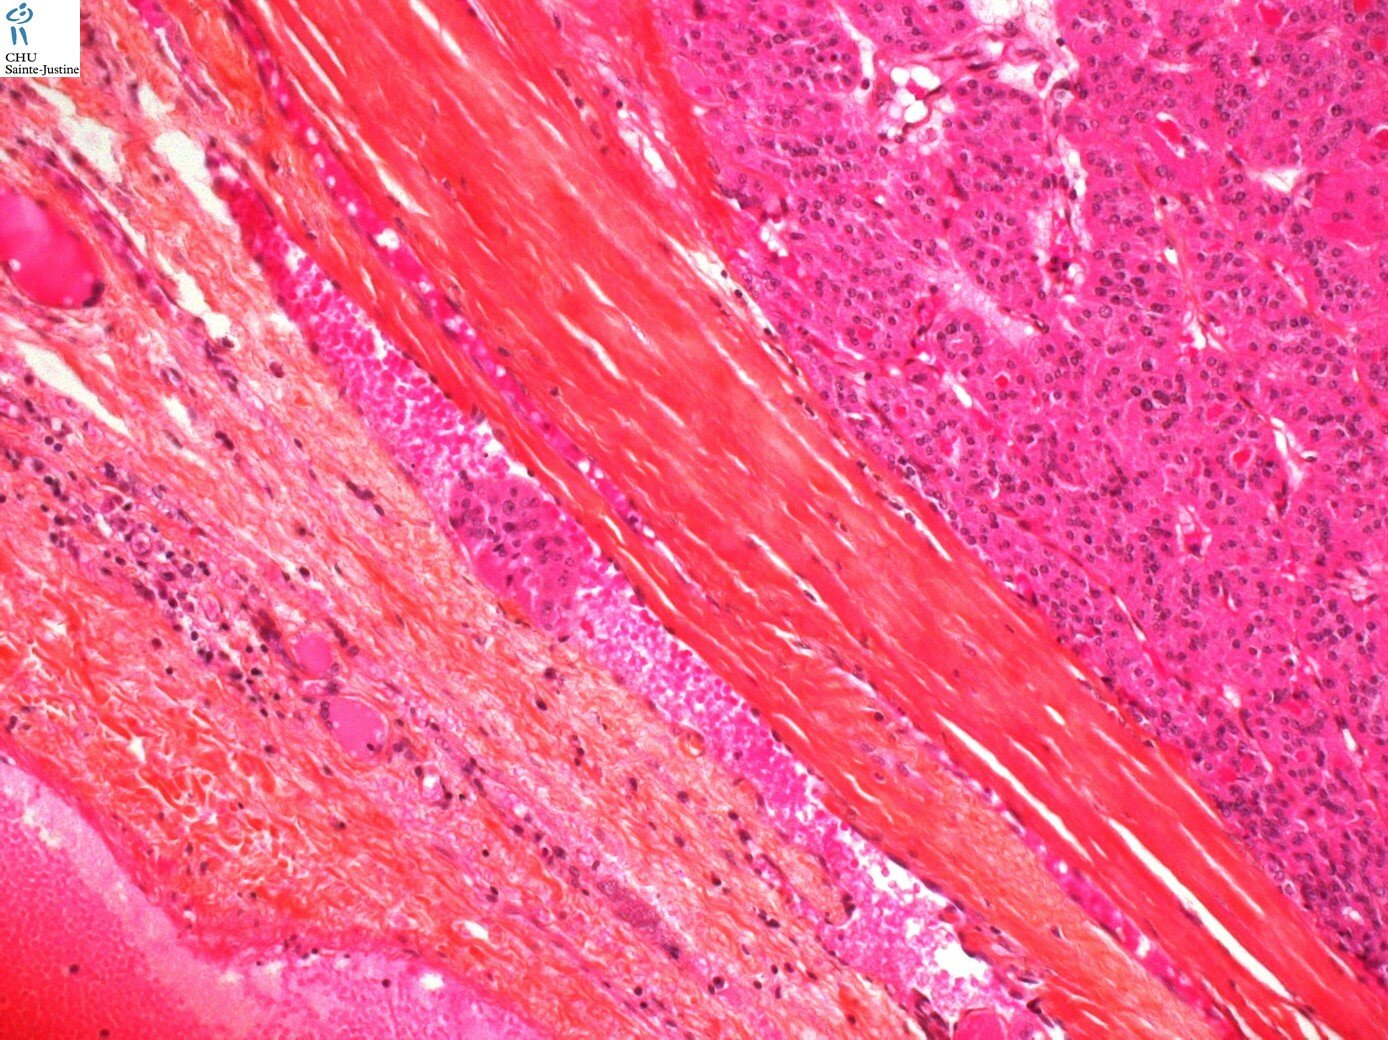

thyroid oncocytic tumors

thyroid oncocytic tumor, Hurthle cell neoplasms of the thyroid

thyroid oncocytic adenoma

thyroid oncocytic carcinoma